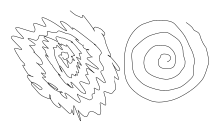

| Archimedean spiral drawings from a man with a unilateral essential tremor. The spiral on the left was drawn by the subject using the left hand, and the one on the right using the right hand. | |